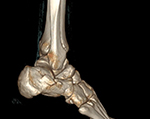

If you are a candidate for an ankle replacement, we will then obtain a CT (computed tomography) scan with multiple views creating a 3D assessment of your unique anatomy.

Your knee will be included in the CT scan to further improve alignment.

The CT scan allows us to create the patient-specific parameters used to plan and perform your surgical procedure with enhanced accuracy.